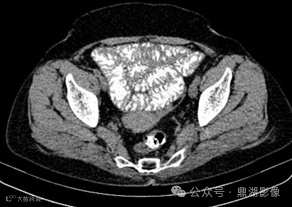

患者,女,55岁,长期腹泻、体重减轻和缺铁性贫血。

CT小肠造影如下

CT增强扫描静脉期

CT小肠造影显示回肠袢轻度扩张,回肠皱襞增多、空肠皱襞减少,并伴有多个肠系膜淋巴结肿大。未发现肠套叠、狭窄或肿块形成等征象。

空回肠皱襞模式反转

空回肠皱襞模式反转(称为回肠空肠化,空肠皱襞减少,回肠皱襞增加)是乳糜泻最特异的征象,文献报道其敏感性和特异性(阳性预测值和阴性预测值)接近100% 。 5cm距离内回肠皱襞数量多于空肠皱襞数量时,则被认为是阳性。

CT和MR小肠造影中,空回肠皱襞模式反转和肠系膜淋巴结肿大是乳糜泻的特征性表现。疾病的严重程度差异极大,从节段性受累到弥漫性小肠受累不等,但最常累及近端空肠。

在CT和MR小肠造影图像上观察到每英寸(=2.54cm)肠段的皱襞少于或等于3个,则认为空肠皱襞密度降低。在重度乳糜泻中,空肠皱襞可能完全消失。在慢性炎症的情况下,回肠皱襞密度可能代偿性增加,定义为每英寸超过5个皱襞,以增加小肠表面积。皱襞数量的增加代表回肠对空肠吸收能力下降的一种适应。